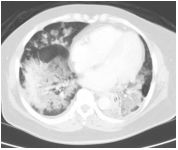

4. 39 y/o female, productive cough for 2 months